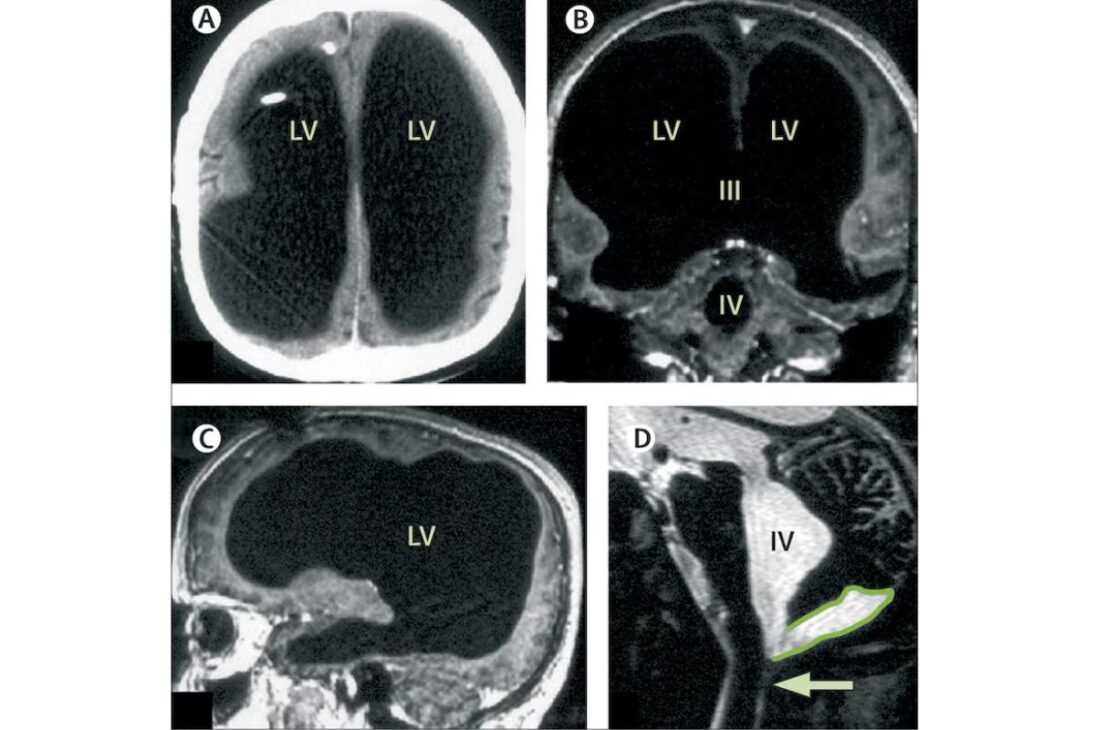

A los 44 años, un francés buscó un hospital tras notar debilidad en la pierna y acabó entrando a una lista diminuta de casos que desafían el sentido común sobre el cerebro. Los exámenes mostraron el cráneo ampliamente lleno de líquido, con solo una fina capa de tejido cerebral preservada, una condición descrita como hidrocefalia.

En el caso descrito, la imagen que sorprendió a los investigadores fue precisamente la desproporción: mucho líquido, poco tejido cerebral visible, aun así con funcionamiento cotidiano preservado.

Aquí, la hipótesis más plausible presentada por investigadores es que la compresión haya ocurrido de forma lenta, permitiendo reorganización funcional gradual, en lugar de un daño agudo y abrupto que derribara capacidades inmediatamente.

Lo que aparece, de forma más consistente, es un cerebro operando con menos tejido disponible que el estándar, pero probablemente con circuitos reorganizados a lo largo del tiempo.